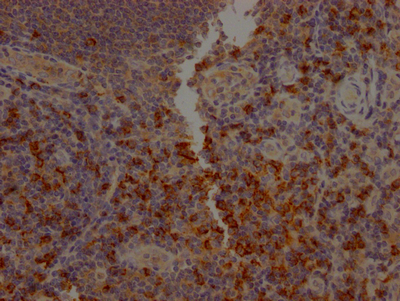

IHC image of CSB-RA934881A0HU diluted at 1:100 and staining in paraffin-embedded human tonsil tissue performed on a Leica BondTM system. After dewaxing and hydration, antigen retrieval was mediated by high pressure in a citrate buffer (pH 6.0). Section was blocked with 10% normal goat serum 30min at RT. Then primary antibody (1% BSA) was incubated at 4℃ overnight. The primary is detected by a Goat anti-rabbit IgG polymer labeled by HRP and visualized using 0.05% DAB.